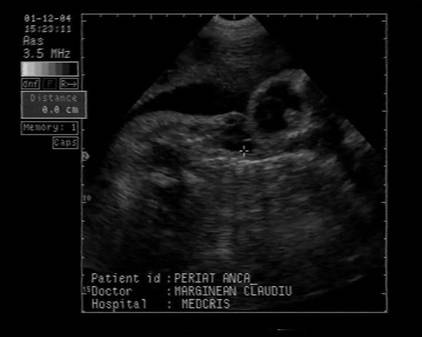

Fig. nr.251 Ciclopia din imaginea precedenta ,cu defect de inchidere pe linia mediana a fetei